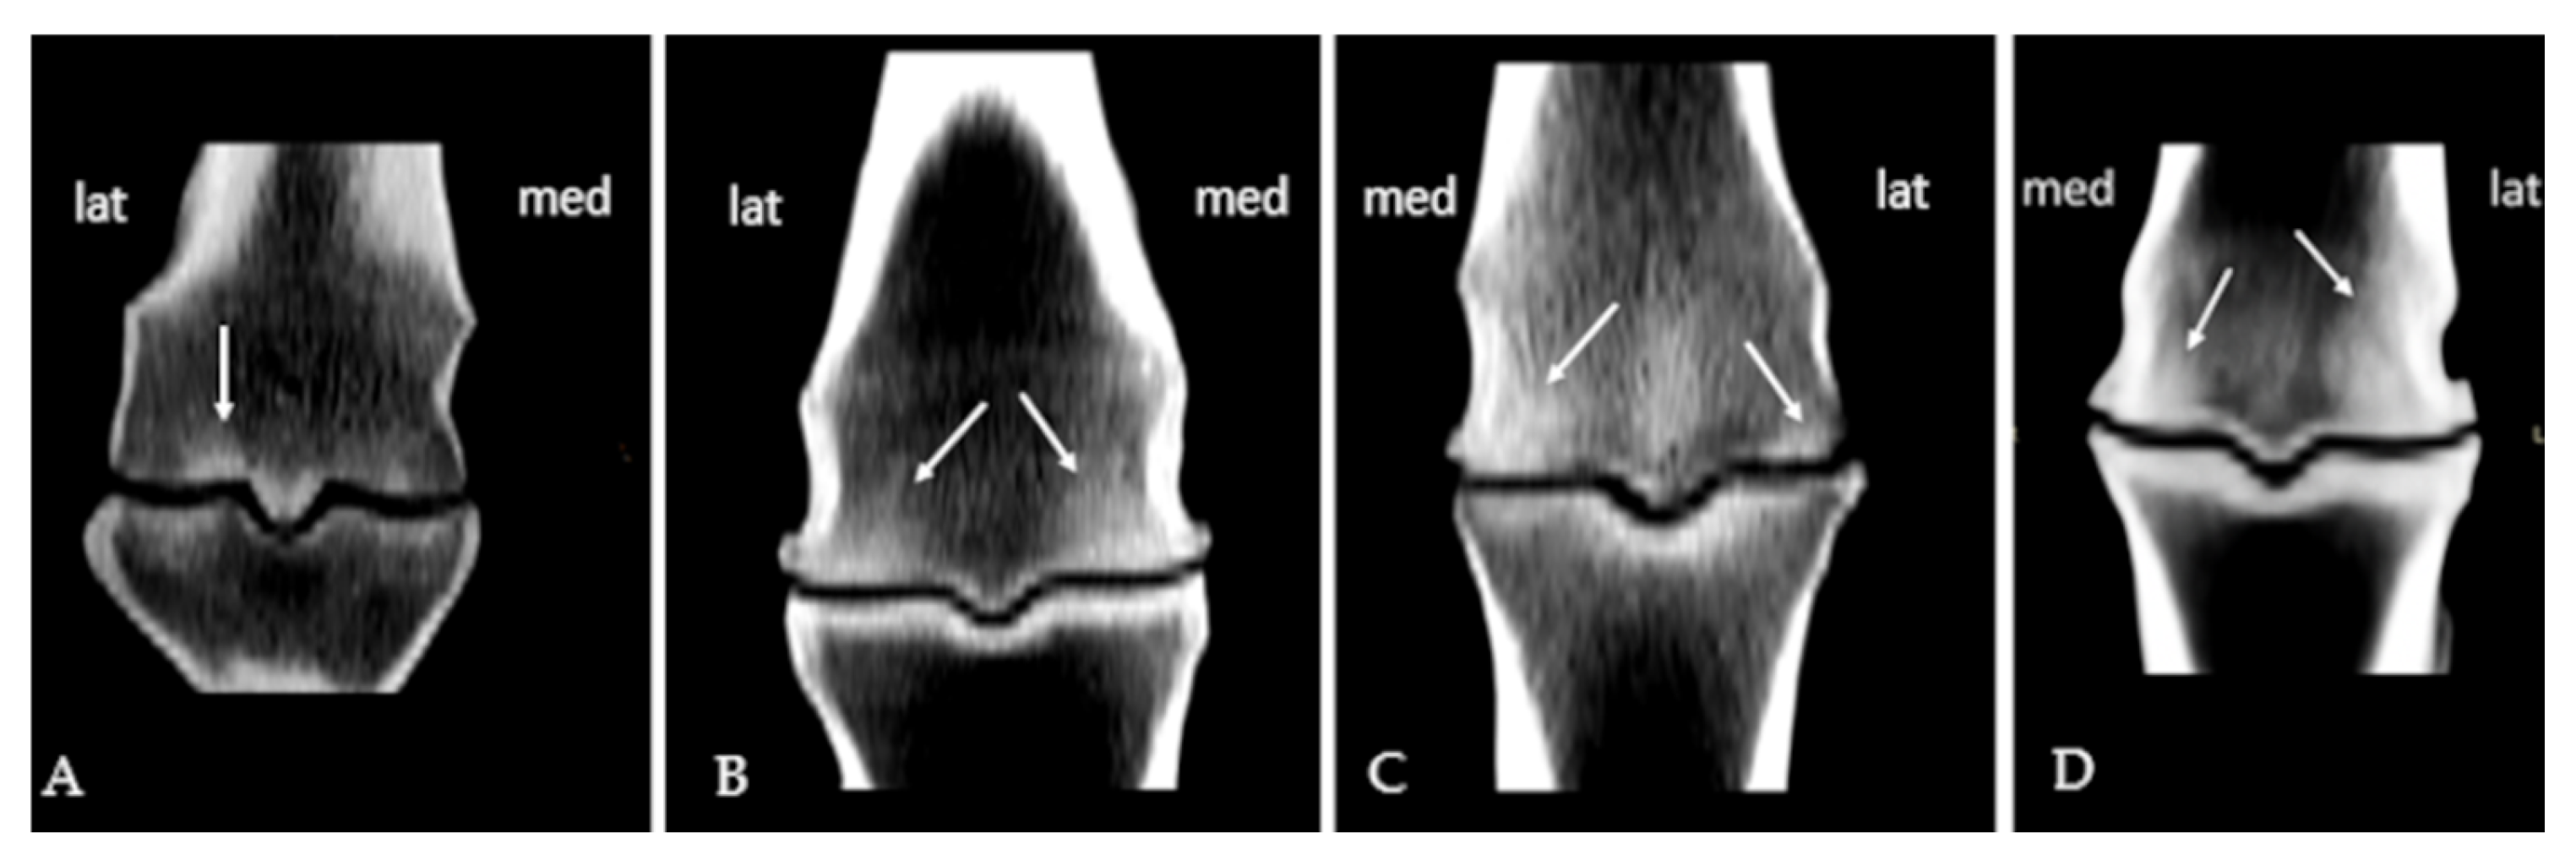

3.1. Subchondral Sclerosis Presence

3.2. Osteophytes Presence